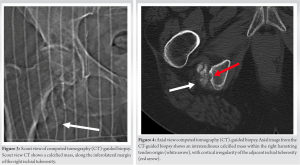

Axial CT images (Fig. 4) revealed that the calcified mass was located within the hamstring tendon origin, with cortical irregularity of the adjacent right ischial tuberosity. The presence of intratumoral calcifications was consistent with an internal chondroid matrix. Histological analysis of the biopsy (Fig. 5) revealed significant deposits of calcium pyrophosphate crystals associated with benign chondroid tissue.

In our case, the imaging findings of the CCMN revealed an amorphous calcified mass projecting inferiorly to the right ischial tuberosity on radiographs. MRI showed cortical irregularity of the ischial tuberosity and demonstrated a calcified low to intermediate T1W signal intensity intratendinous soft-tissue mass within the hamstring tendon origin. The mildly increased T1W signal within the tumor may be attributed to a combination of intratumoral protein content and T1 shortening due to surface interactions between microcalcifications and protons [7,8]. In addition, intralesional foci of high signal intensity were observed on proton density images, which likely corresponded to the chondroid/cartilaginous matrix of the neoplasm. Notably, there was minimal perilesional edema on fluid-sensitive sequences, which serves as a distinguishing feature from acute calcific tendinitis. Post-contrast imaging revealed a heterogeneously enhancing solid soft-tissue mass. The scattered internal foci with low signal intensity on both T1 and PD sequences were suggestive of internal mineralization within the mass. CT images (Figs. 3 and 4) further revealed mass-like amorphous calcifications within the right hamstring tendon origin, causing cortical irregularity in the adjacent ischial tuberosity.